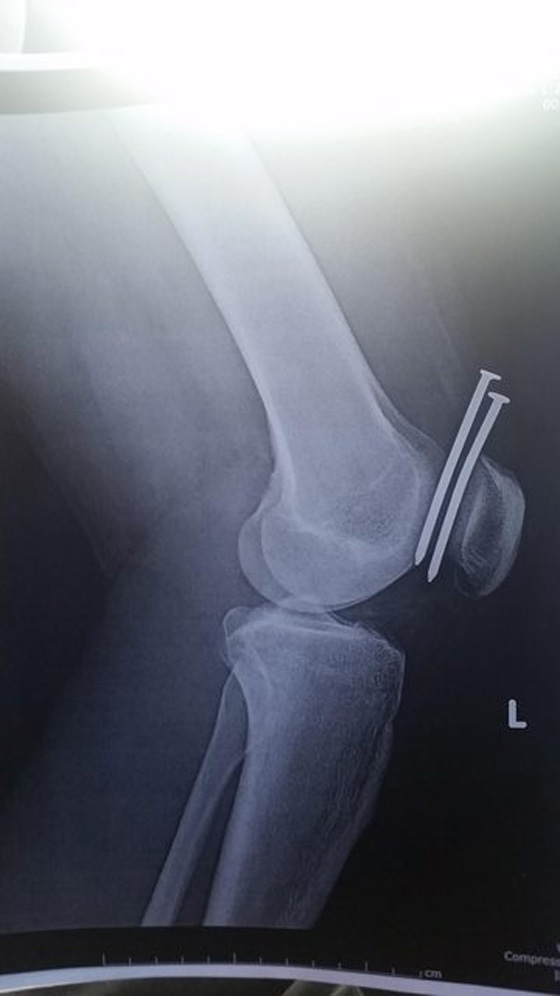

نجا نجار متدرب بأعجوبة من إصابة مروعة بعدما صوب مسدس مسامير في اتجاه ركبته. وقضى الشاب يومه الثاني من التدريب في تأطير الأخشاب داخل موقع بناء في شيكاغو عندما ضغط على خرطوم الغاز المتصل بالمسدس، حيث اهتز بشدة وبدأ بإطلاق المسامير على ركبته. بعد وقوع الحادث، قام مجموعة من زملائه بنقله إلى المستشفى، وأبلغه الأطباء في وقت لاحق أنه نجا بأعجوبة من الحادث، فقد كادت المسامير أن تقطع الشريان الرئيسي في الفخذ. وقال الأطباء إن 6 جراحين أجروا عملية جراحية خطيرة للشاب، ووصفوها بأنها معجزة طبية بعد أن عجزت الأدوية على زحزحة المسامير.